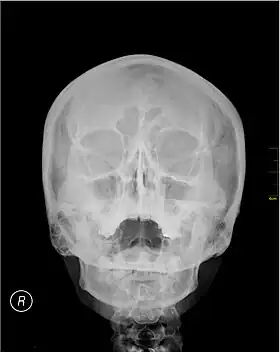

Waters' view (also known as the occipitomental view) is a radiographic view of the skull. It is commonly used to get a better view of the maxillary sinuses. An x-ray beam is angled at 45° to the orbitomeatal line. The rays pass from behind the head and are perpendicular to the radiographic plate. Another variation of the waters places the orbitomeatal line at a 37° angle to the image receptor. It is named after the American radiologist Charles Alexander Waters.

Waters' view can be used to best visualise a number of structures in the skull.

- Maxillary sinuses.

- Frontal sinuses, seen with an oblique view.

- Ethmoidal cells.

- Sphenoid sinus, seen through the open mouth.

- Odontoid process, where if it is just below the mentum, it confirms adequate extension of the head.

Typically, the x-ray beam is angled at 45° to the orbitomeatal line.[3] Another variation of the waters places the orbitomeatal line at a 37° angle to the image receptor,[4] or 30°.[5]